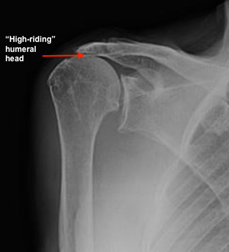

Carefully standardized X-rays reveal the loss of the space between the hu¬meral head and glenoid that is normally occupied by cartilage, leaving bone on bone contact. There is “high-riding” of the humeral head compared to the socket due to the absence of the rotator cuff tendons. CT scans and MRI studies can be helpful in providing additional information about bone quality and the soft tissues surrounding the shoulder joint.

- Shoulder with Rotator Cuff Arthropathy